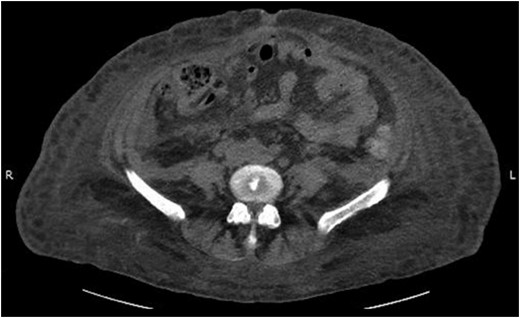

Her intra-abdominal bladder pressure (IAP) was noted to be 31 mm Hg (Grade IV intra-abdominal hypertension). The patient was emergently taken to the operating room (OR) for abdominal decompression. Necrotic rectus muscle was noted when the fascia was transected. Two liters of organized clot and blood was removed which had dissected into the retroperitoneal space bilaterally. After the damage control laparotomy, the patient was admitted to the surgical ICU with temporary abdominal wall closure achieved by application of Abthera™ ‘Vacuum Assisted Closure’ (KCI, San Antonio, TX, USA). Patient was taken back to the OR within 24 h for re-exploration and abdominal fascial closure. She recovered very well from her surgery with normalized bladder pressures and complete recovery of renal function. A repeat CT scan on postoperative Day 10 showed complete resolution of her rectus sheath and retroperitoneal hematomas (Fig. 3).

Abdominal CT scan showing complete resolution of rectus sheath and retroperitoneal hematomas.